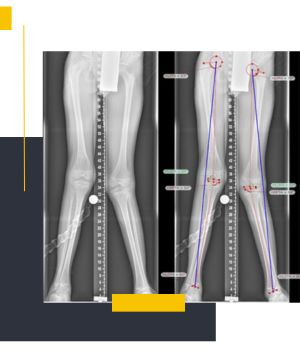

استفاده از دستگاههای دیجیتال نسل جدیدکیفیت بالای تصاویر و نمایش دقیق محور پا باعث میشود تشخیص و ارزیابی پزشکان با اطمینان بیشتری انجام شود.

تهیه عکس در حالت ایستاده برای بررسی واقعی محور اندام

عکسهای الایمنت ویو در مروارید ری طبق استانداردهای ارتوپدی و در وضعیت صحیح ایستاده گرفته میشود تا نتیجه کاملاً دقیق و قابل اعتماد باشد.

تیم مجرب مرکز با انجام روزانه تعداد زیادی از تصاویر اندام تحتانی مهارت بالایی در ثبت درست زاویهها و محورهای استخوانی دارد.